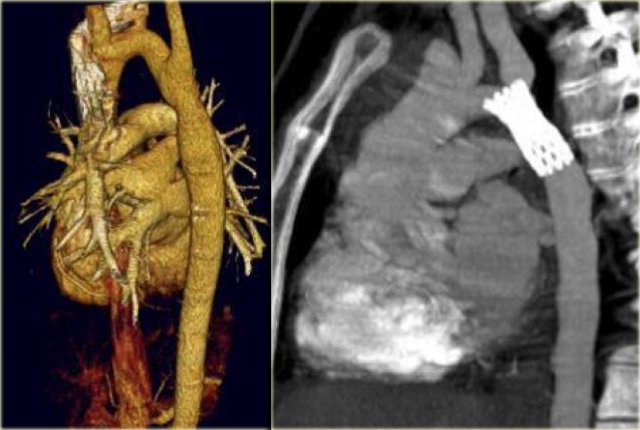

Coarctation treated with angioplasty (left) and stent placement (right) Coarctation treated with angioplasty (left) and stent placement (right)

Coarctation is treated with angioplasty, stent placement or patch aortoplasty.

The image on the far left is the result after angioplasty.

Next to it a patient who was treated with a stent.

Notice that the stent is obstructing the orfice of the left subclavian artery.

Pseudo-aneurysm in coarctation treated with stent-placement Pseudo-aneurysm in coarctation treated with stent-placement

On the far left a patient who was treated with a stent.

The stent ruptured causing restenosis.

Next to it two patients with pseudo-aneurysm.

One after angioplasty and another who developed a pseudo-aneurysm after stent placement.

They have to be repaired because they will rupture.

Pseudo-aneurysms are seen in

• 10% after angioplasty.

• 30% after patch aortoplasty.